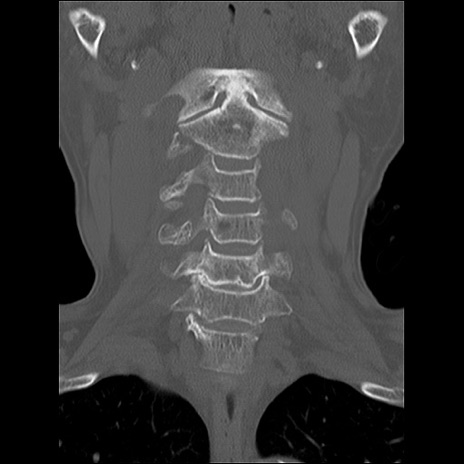

症例48 頚椎CT(冠状断像)

頚椎CT